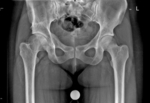

Bækken og hofte (traume)

AP af bækken

Lejring:

Liggende i rygleje. Hvis muligt med benene 15° indadroteret.

Rørkipning:

0°.

Centrering:

3 fingersbredder over symfysen.

Kriterier:

Crista iliaca, trochanter major og kringlerne skal fremstilles.

Bemærkning:

Der tages altid AP af bækken uden kalibreringskugle og et lavt bækken med kalibreringskugle mellem proximale femoris.